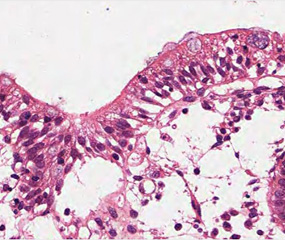

괴사 소장결장염